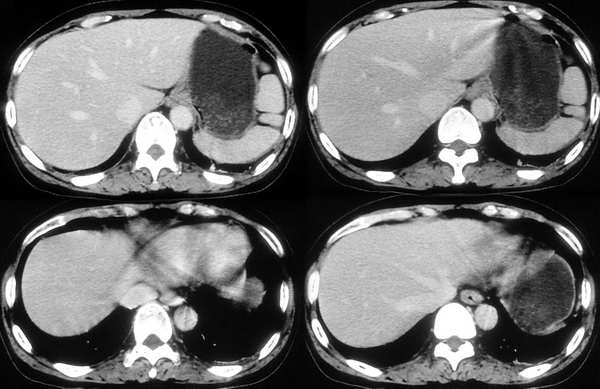

[br]请问战友,肝左叶低密度影和增强后杂乱无章的血管是什么?这是正常的吗?

以下是引用向医生在2005-11-3 21:54:00的发言:[br][br] 我觉得这例除了胆囊结石可以肯定外,肝左叶低密度区考虑为病灶尚不可靠。[br] 在b超下,早期肝脓肿者肝内见较强回声,界限欠清、模糊、形态不规则,如果有坏死液化才会出现低回声,而本例超声下已见低回声,如果真是这种情况的话就是说明病灶内已有坏死液化,这些液化区在ct增强下应该表现为低密度影,本例增强并无这样改变,所以b超的结果可不可靠值得怀疑。[br] 胆囊结石合并胆囊炎也可出现畏寒、发热及白细胞增高等,抗炎治疗后也可症状缓解,不一定非要用肝脓疡来解释。